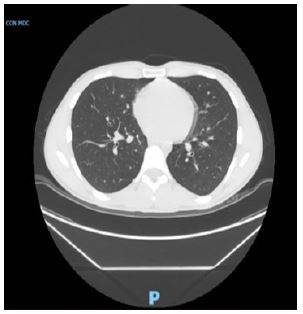

Supportive treatment included oxygen via Venturi mask (FiO2 0.5), inhaled salbutamol, and a single dose of intravenous furosemide (20 mg). The patient’s respiratory status improved over the following 48 hours. Repeat imaging on day 3 showed near-complete resolution of pulmonary edema. The patient was discharged home in stable condition on postoperative day 3 (Figure 3A & 3B).

Images are Not Display Check it

Figure 3: Radiographic images of the chest on day 2 (A) and day 3 (B) of hospitalization revealed improvement in pulmonary edema and nearly resolution of pulmonary edema, respectively.